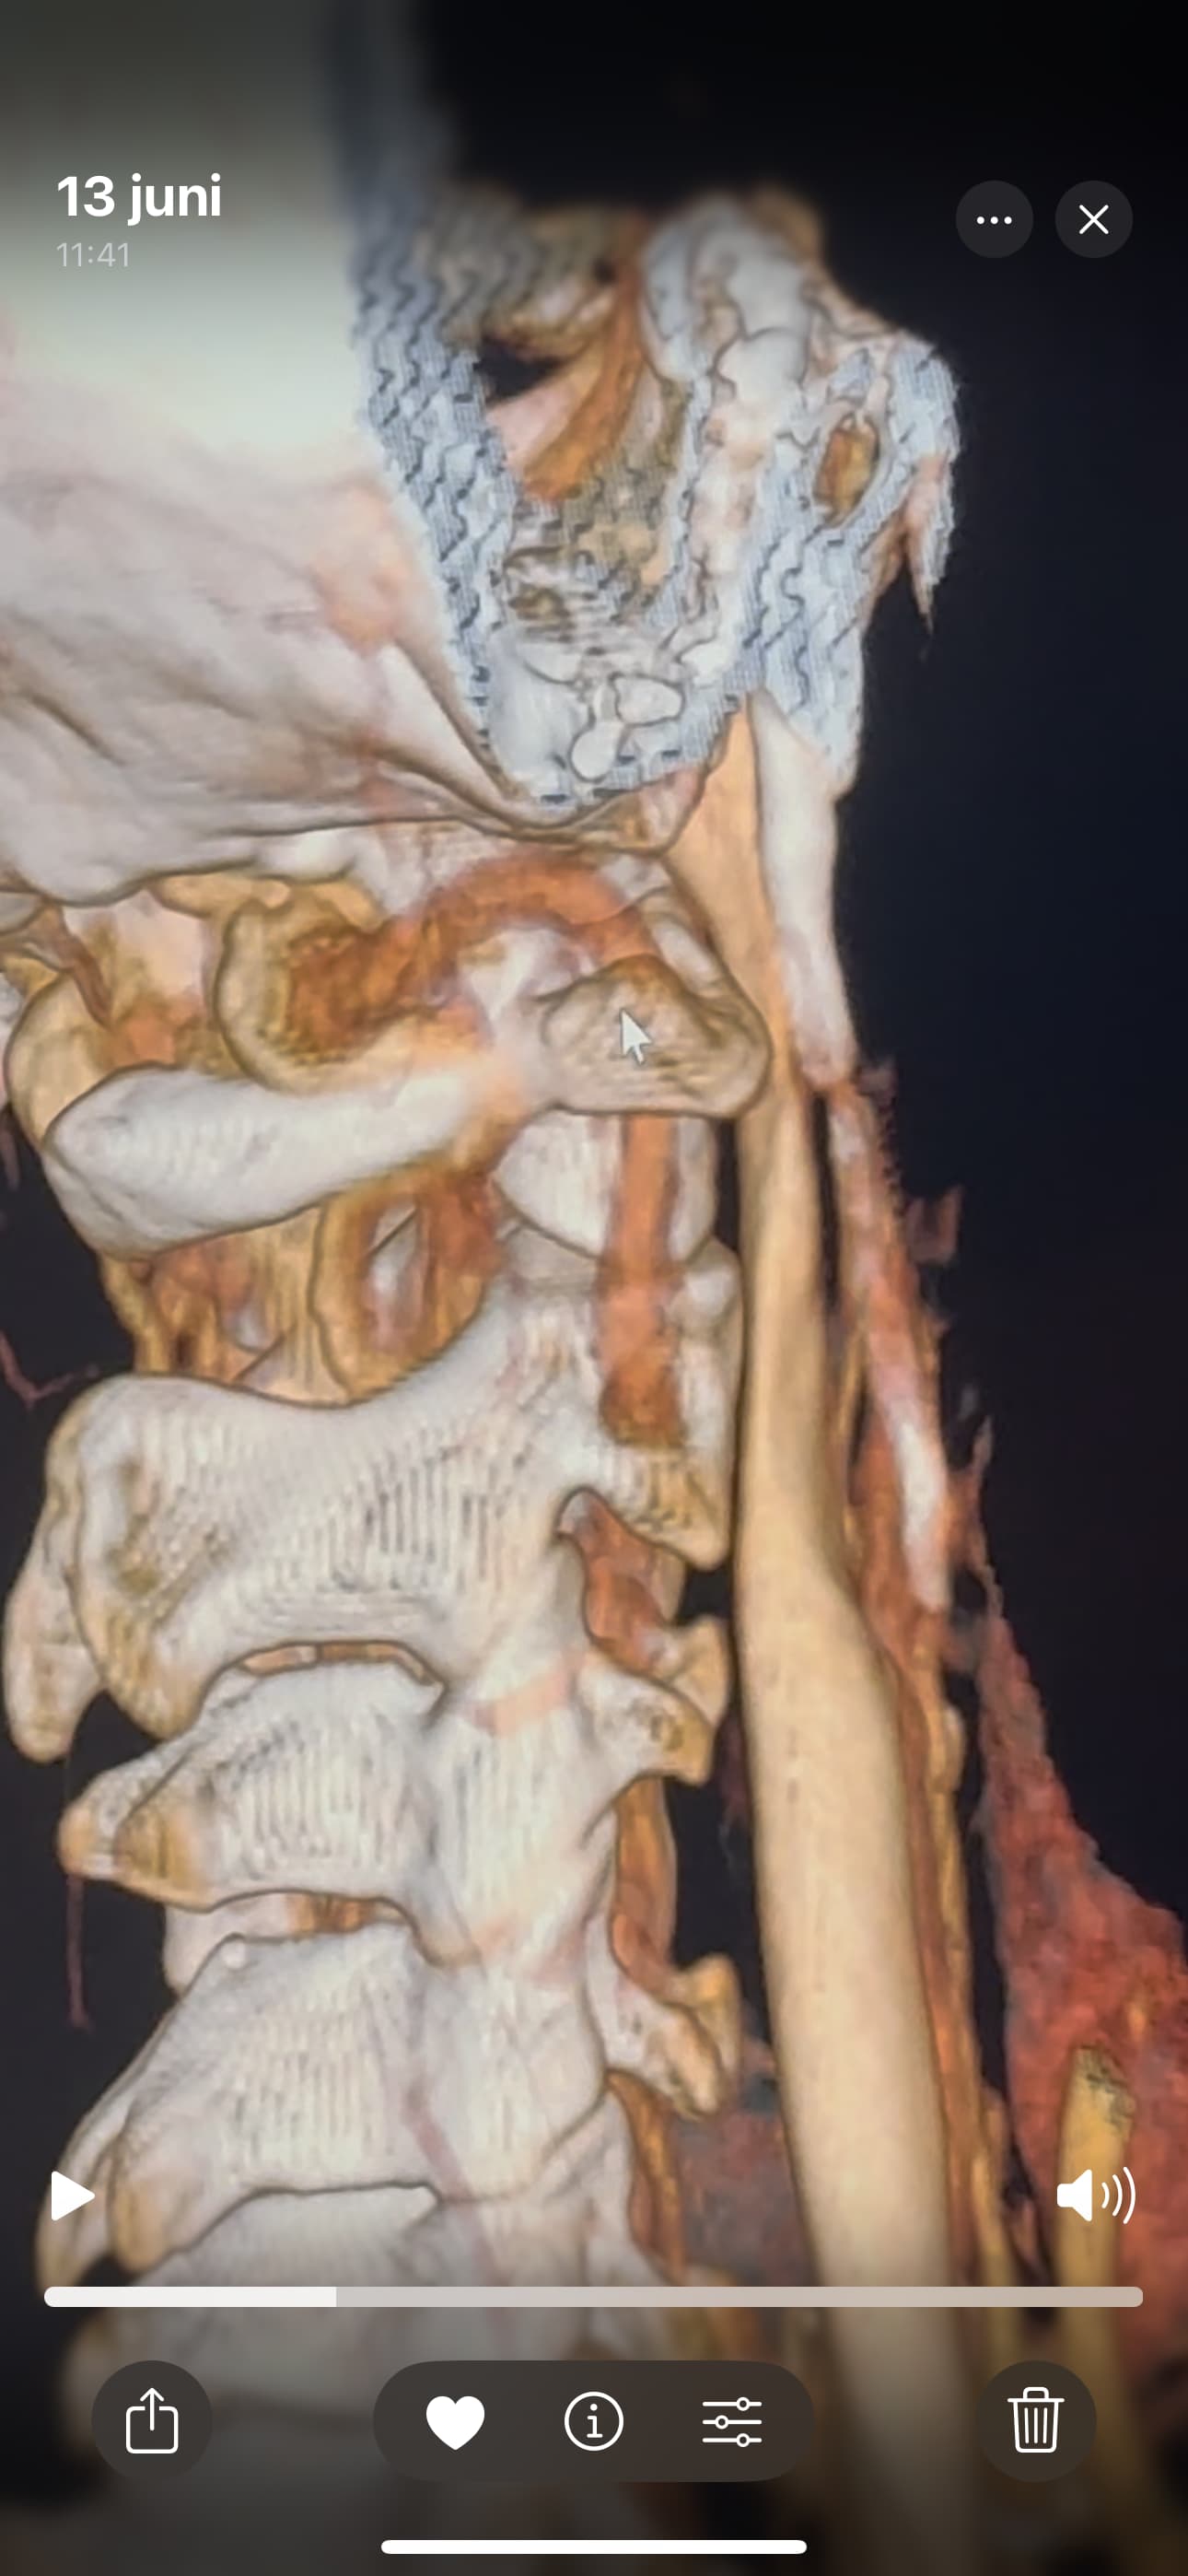

@Rob12345 can you go into the axial view of the original imaging and go to C1? It’s the best view for showing IJV compression by C1 and styloids. I’ve attached my own imaging to help you find C1 in the axial view.

@Rob12345 - I can see you have bilateral IJV compression in the images you’ve posted & it’s possible the middle image in your first set of pictures is pointing to collateral veins. I’m not great at identifying collaterals, but I can say for sure your IJVs are being squashed between your styloids & C1.